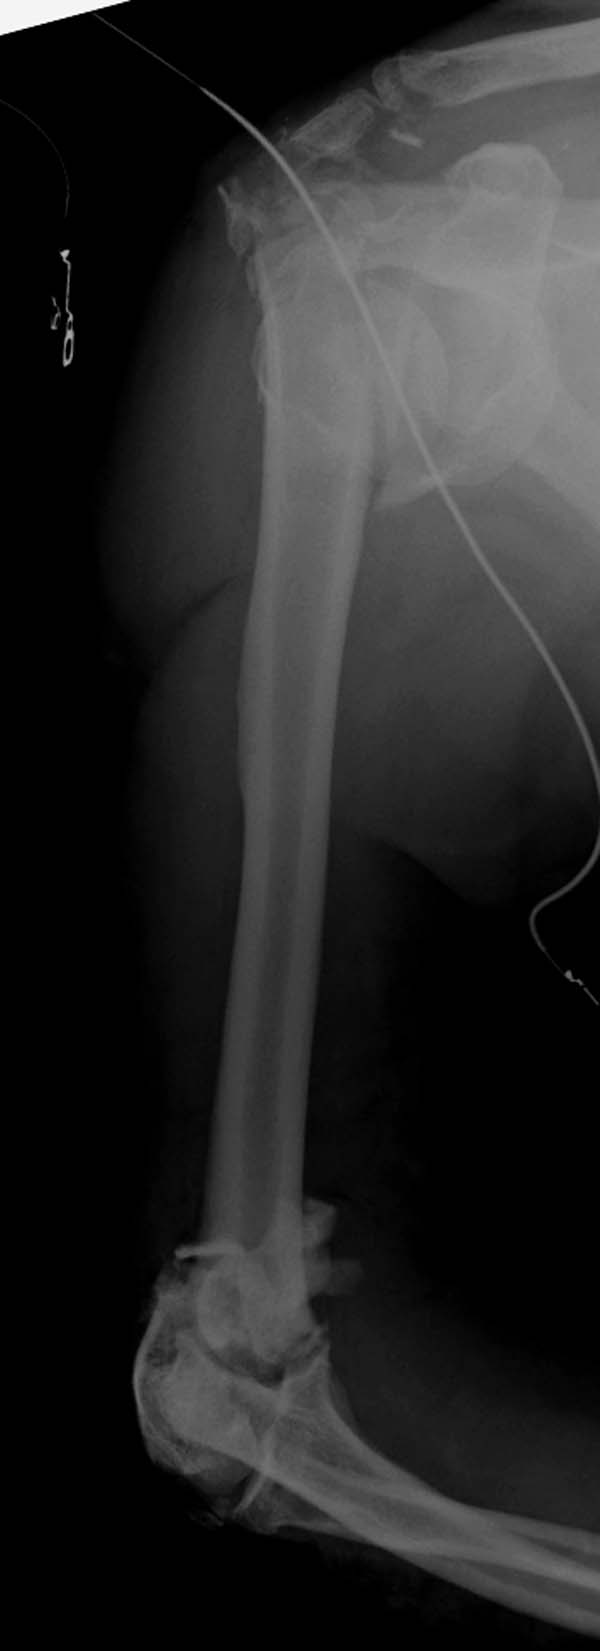

Примеры: первому более 15 лет фиксирован шурупом и tension band

technique, а второй перелом открытый больной 80 лет, после наружного

фиксатора в первом этапе и окончательная фиксация вторично. Третьий раз

внесуставная остеотомия...

Имя     : 3-1 Humerus prox distal.jpg

Тип     : image/jpeg

Размер  : 41125 байтов

Описание: отсутствует

Url     : http://weborto.net:8080/pipermail/ortho/attachments/20130604/c45a379f/attachment-0027.jpg